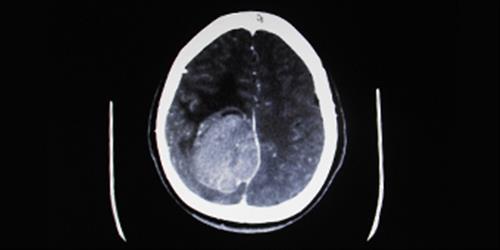

Teşhiste kullanılan tetkik yöntemleri: beyin tomografisi (BT) beyin manyetik rezonans görüntüleme (MRG). Bu test yöntemleri ile beyin tümörü yerleşimi, cinsi, hakkında ve büyüklüğü hakkında çabuk ve kısa sürede bilgi alınır.